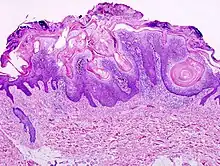

Visual diagnosis is made by the "stuck on" appearance, horny pearls or cysts embedded in the structure. Darkly pigmented lesions can be challenging to distinguish from nodular melanomas.[12] Furthermore, thin seborrheic keratoses on facial skin can be very difficult to differentiate from lentigo maligna even with dermatoscopy. Clinically, epidermal nevi are similar to seborrheic keratoses in appearance. Epidermal nevi are usually present at or near birth. Condylomas and warts can clinically resemble seborrheic keratoses, and dermatoscopy can be helpful. On the penis and genital skin, condylomas and seborrheic keratoses can be difficult to differentiate, even on biopsy.

A study examining over 4000 biopsied skin lesions identified as seborrheic keratoses showed 3.1% were malignancies. Two-thirds of those were squamous cell carcinoma.[13] To date, the gold standard in the diagnosis of seborrheic keratosis is represented by the histolopathologic analysis of a skin biopsy.[14]